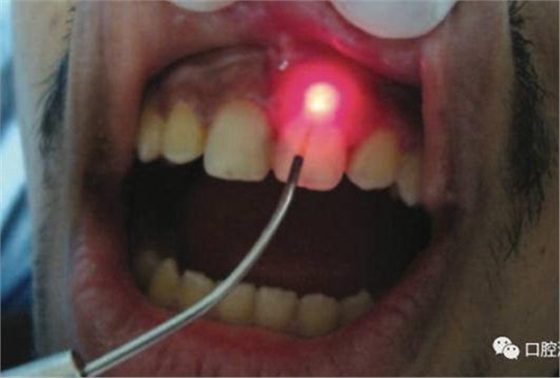

對瘺管位置進(jìn)行激光氣化

激光治療后即刻